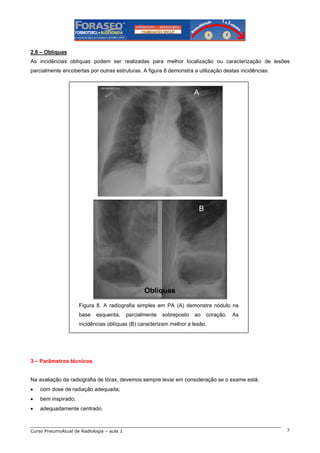

2.6 – Oblíquas

As incidências oblíquas podem ser realizadas para melhor localização ou caracterização de lesões

parcialmente encobertas por outras estruturas. A figura 8 demonstra a utilização destas incidências.

A

B

Figura 8. A radiografia simples em PA (A) demonstra nódulo na

base

esquerda,

parcialmente

sobreposto

ao

coração.

As

incidências oblíquas (B) caracterizam melhor a lesão.